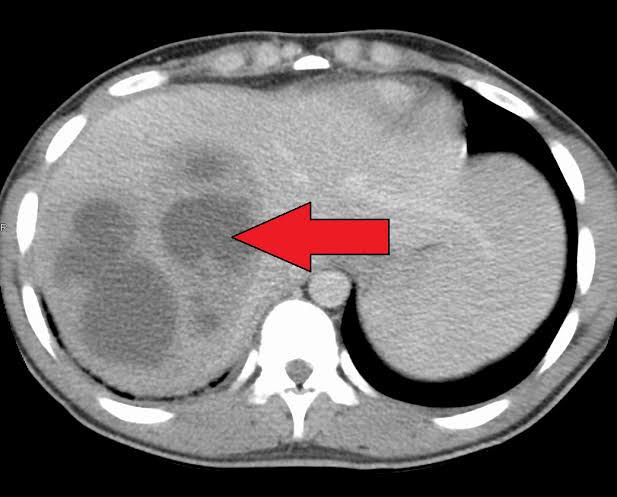

Pyogenic liver abscess is a pus-filled pocket of fluid within the liver. Pyogenic means producing pus. A liver abscess can develop from several different sources, including a blood infection, an abdominal infection, or an abdominal injury which has been become infected.